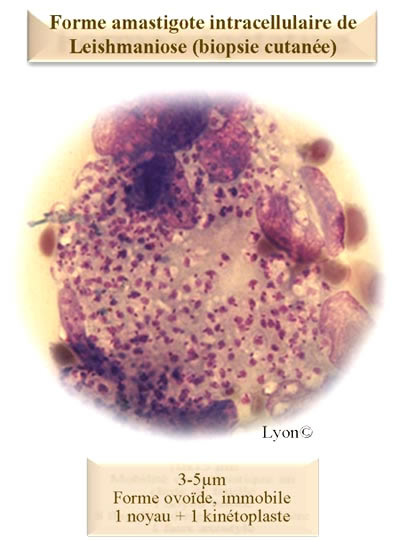

Leishmania sp.